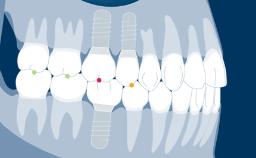

Implant-supported fixed dental prostheses aim to provide replacements for missing teeth that are able to withstand functional demands and accurately mimic the esthetics of the missing dental units.

To achieve this goal, the clinician must select the best available materials to meet the challenges posed by the clinical situation.

This module will discuss the dental materials that are available for the manufacture of implant-supported fixed dental prostheses and the basic principles involved in selecting the material that is best suited for each case.